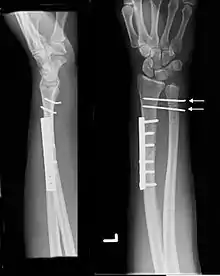

The Galeazzi fracture is a fracture of the distal third of the radius with dislocation of the distal radioulnar joint. It classically involves an isolated fracture of the junction of the distal third and middle third of the radius with associated subluxation or dislocation of the distal radio-ulnar joint; the injury disrupts the forearm axis joint.[1]

| Galeazzi fracture. Arrow points at the dislocated ulnar head | |

Galeazzi fractures are best treated with open reduction of the radius and the distal radio-ulnar joint.[3] It has been called the "fracture of necessity," because it necessitates open surgical treatment in the adult.[4] Nonsurgical treatment results in persistent or recurrent dislocations of the distal ulna.[1] However, in skeletally immature patients such as children, the fracture is typically treated with closed reduction.[1]